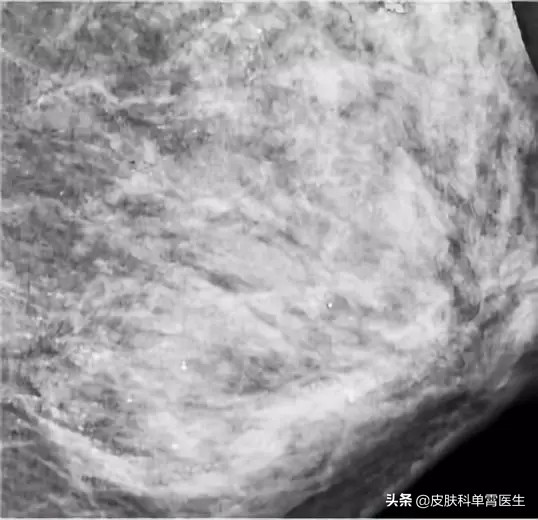

48岁的朱女士亲身体验了一把。在进行乳腺钼靶X线摄影检查时,医生发现朱女士的左侧乳房布满众多细小如沙子一样、呈散在分布的钙化灶,并且无法轻易判断哪些是良性,哪些是恶性。

一般来说,乳房内部出现钙化灶,原因很多:可能是炎症或损伤渗出物留下的痕迹、新陈代谢后的钙盐沉积,也有可能是肿瘤造成的组织变化。

医生询问朱女士之后得知,原来朱女士是胸部精油爱好者,常年做按摩。医生分析,“沙粒胸”的出现,极可能是由于按摩时用力不当损伤了腺叶乳管,导致坏死性细小点状钙化。仅凭肉眼无法分辨周围组织是否有癌变风险,也无法确定是否是早期乳腺癌症状,等待朱女士的,很可能是切取、钳取、穿刺等活检手术。